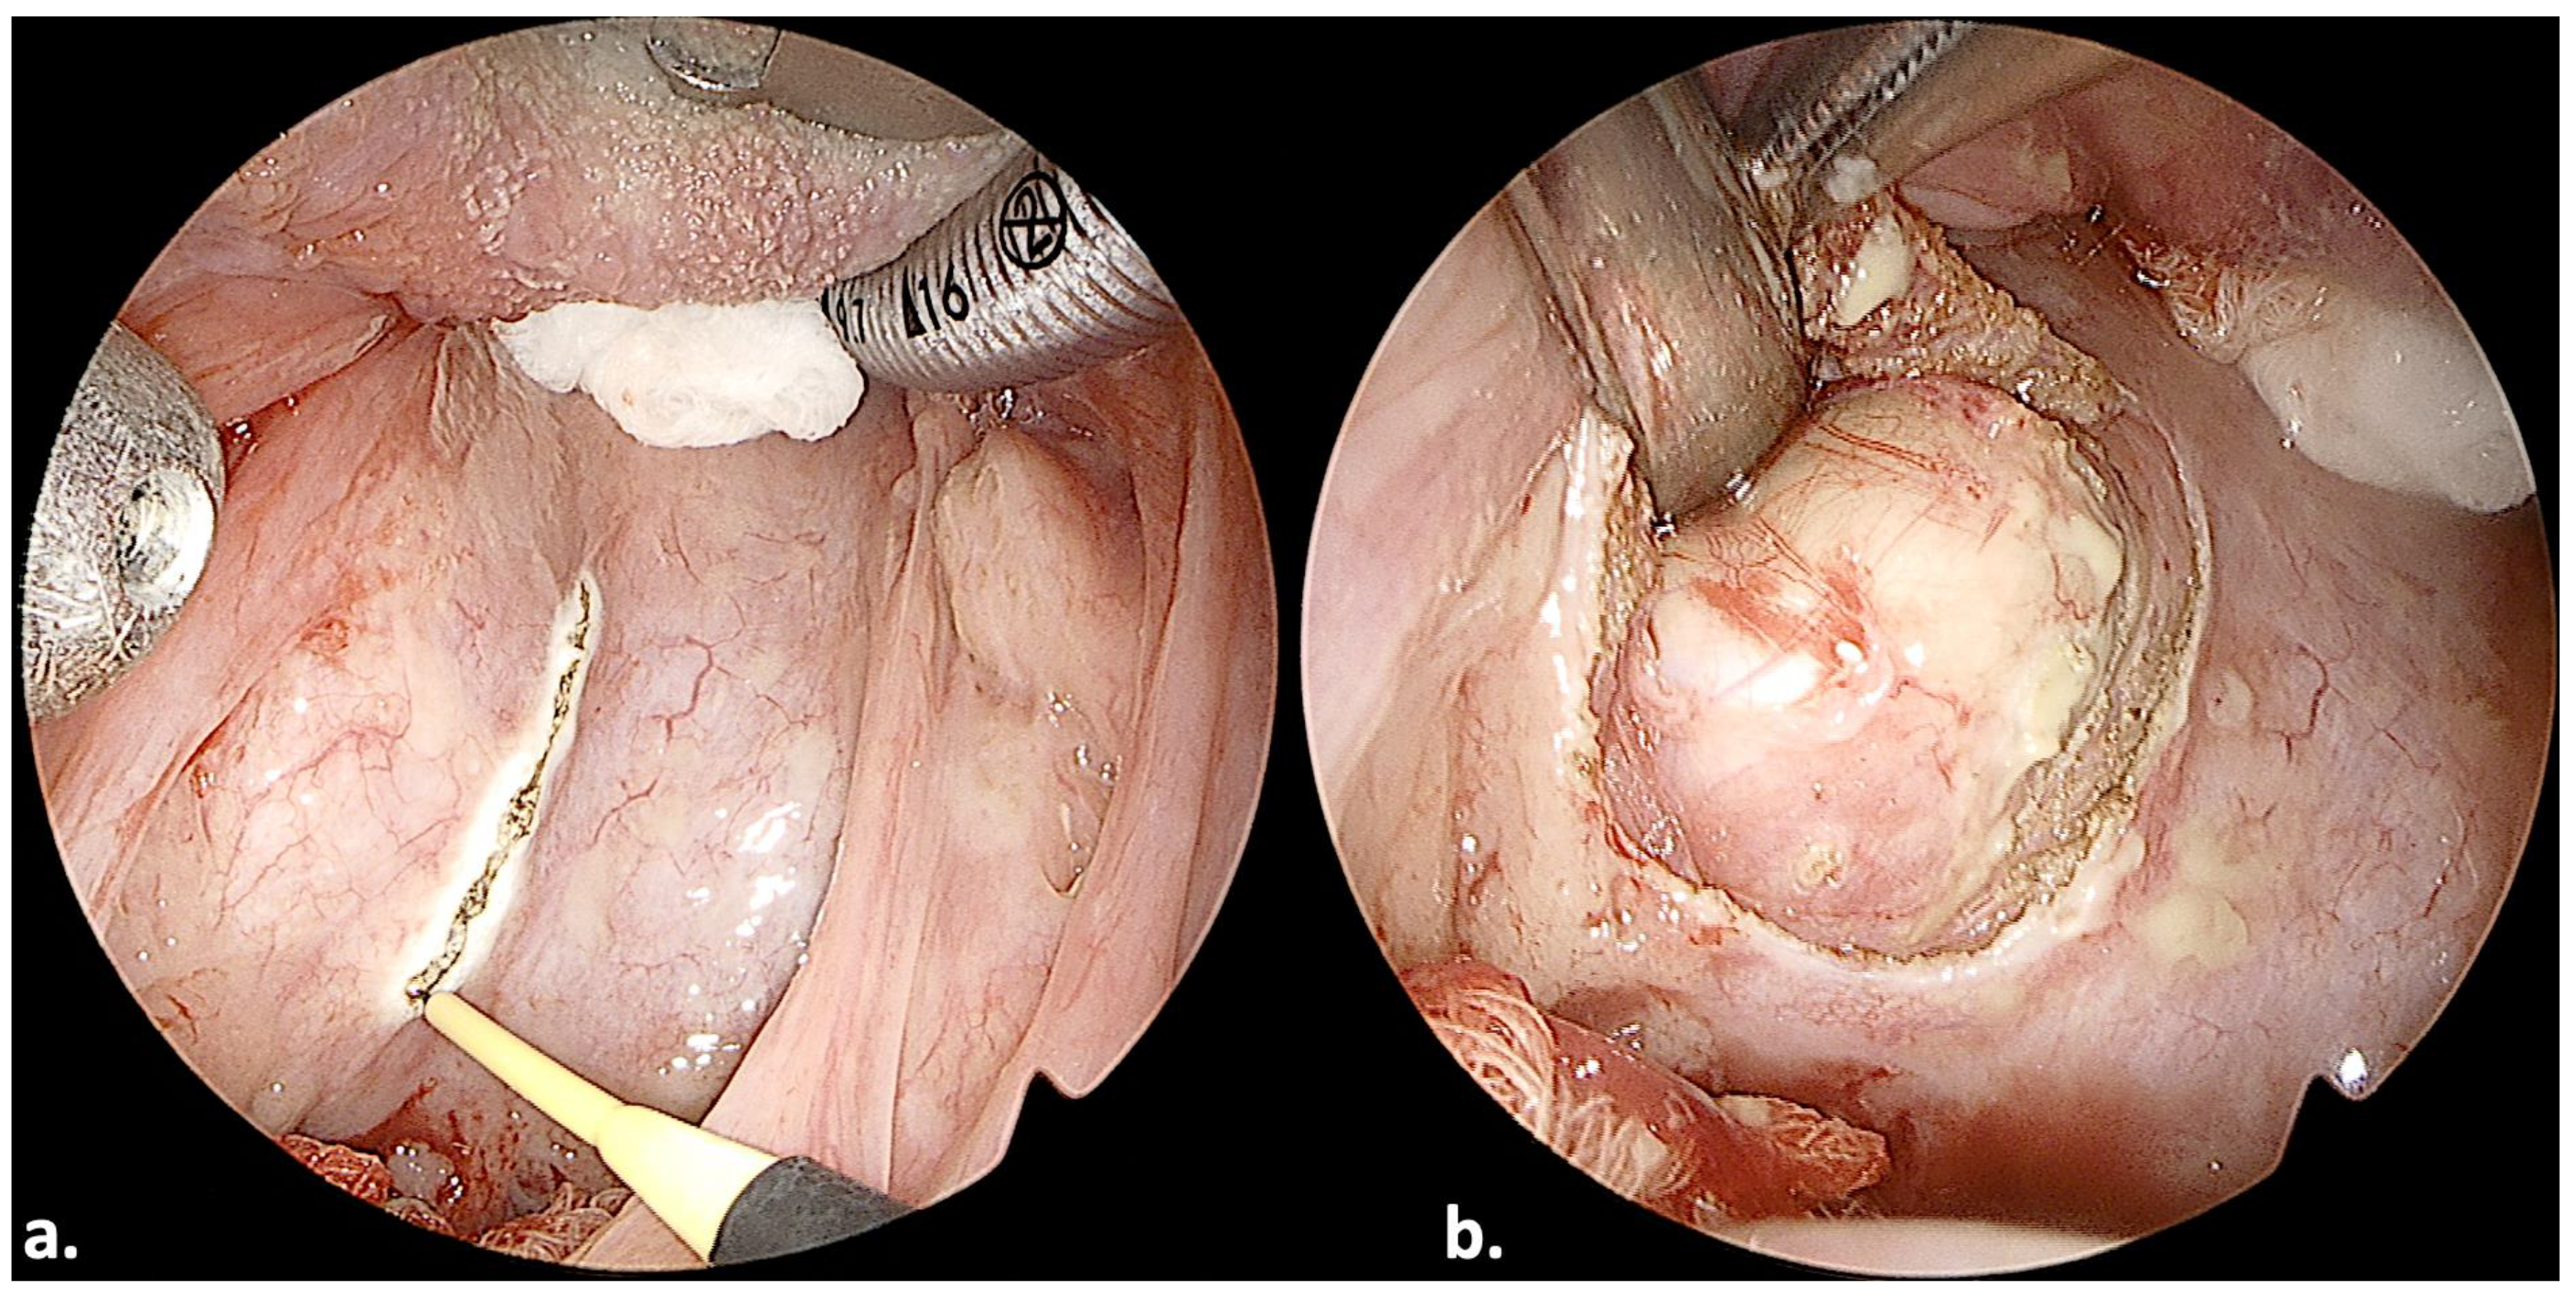

3.2. Case 4

3.5. Case 12